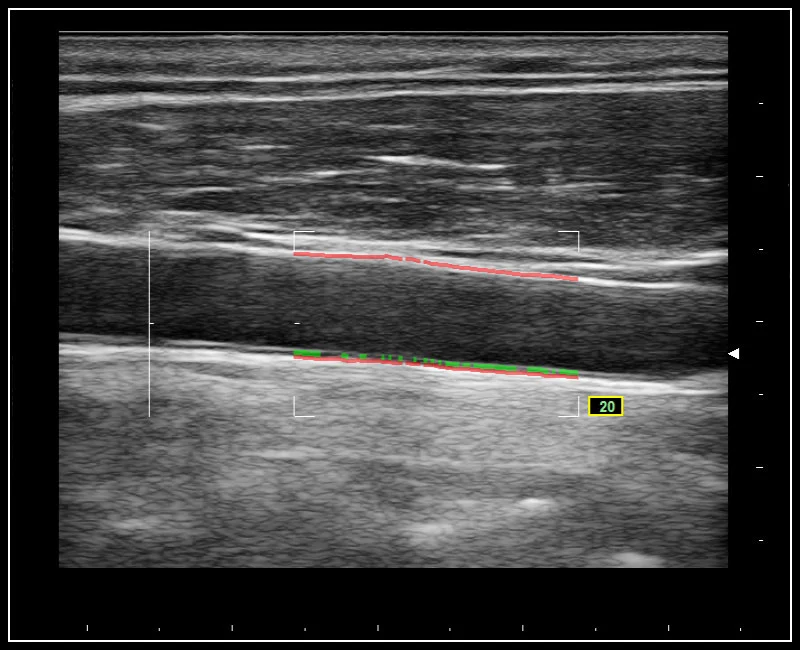

MyLab™9 Platform - QIMT Intima-media thickness quantification based on radio frequencies in real-time studies

MyLab™9 Platform - QIMT Intima-media thickness quantification based on radio frequencies in real-time studies